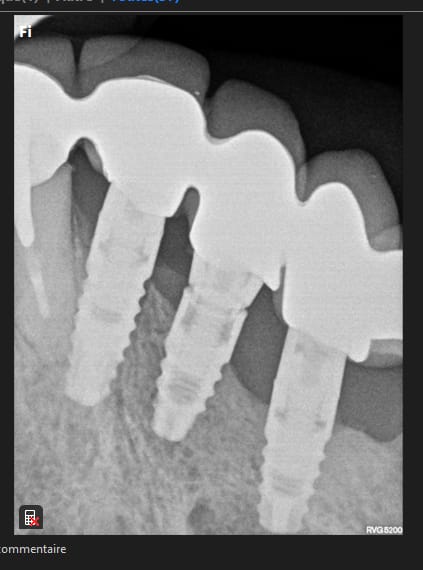

Es ce que quelqu'un aurai la reference de ses implants????

une radio mieux centrée serait idéale pour être certain à 100%.....mais ils ont quand même une bonne gueule de TBR conic....

https://www.spotimplant.com/fr/implants-dentaire/tbr/conic

Merci pour votre retour....je vous met une radio panoramique...j'ai pas mieux desolé....